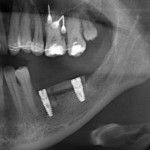

Для пациентов, которым предстоит операция дентальной имплантации, есть статья «Как подготовиться к операции имплантации? Какое обследование необходимо?». Она ответит на вопросы о том, почему необходима компьютерная томография, диагностические модели и консультации смежных специалистов.

И вот, на моем сайте появился раздел с названием Staskins.Hints. В нем собраны памятки с рекомендациями и назначениями в пред- и послеоперационном периоде.

- 0 — Рекомендации перед операцией

(имплантация, остеопластические операции, синуслифтинг) - 1 — Рекомендации после операции

(удаление зуба, удаление новообразований, немедленная имплантация) - 2 — Рекомендации после операции

(имплантация, остеопластические операции, синуслифтинг, зубосохраняющие операции, операции на мягких тканях полости рта).